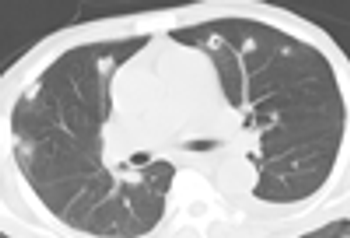

Autosomal dominant polycystic kidney disease (ADPKD) is common. Presenting symtpoms include hypertension, hematuria, proteinuria, and renal insufficiency.